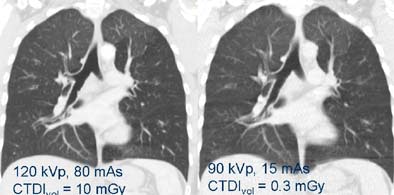

![]() |

| Even extremely low-dose imaging can often answer the relevant clinical questions, especially in high-contrast areas such as the lungs. Image at right was acquired with 1/30th the dose of example at left; both reveal air trapping. Images courtesy of Dr. Mathias Prokop. |